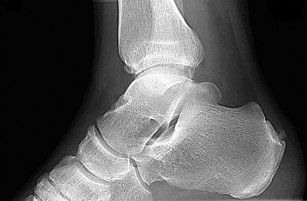

A 16-year-old boy presents with progressive knee pain. Radiographs demonstrate a destructive distal femoral lesion with a 'sunburst' periosteal reaction as shown below. Biopsy confirms high-grade intramedullary osteosarcoma. Following neoadjuvant therapy and surgical resection, what is the single most important prognostic factor for long-term survival?

Explanation

The image and presentation are classic for a conventional high-grade osteosarcoma. While factors like tumor size and alkaline phosphatase have prognostic value, the most critical prognostic indicator for overall survival is the degree of histologic necrosis (typically aiming for >90% necrosis) following neoadjuvant chemotherapy.